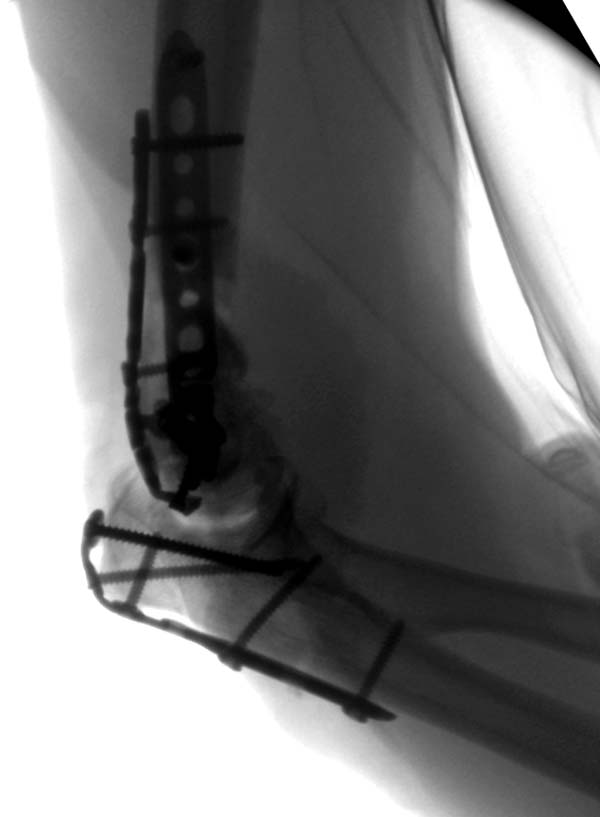

Примеры: первому более 15 лет фиксирован шурупом и tension band

technique, а второй перелом открытый больной 80 лет, после наружного

фиксатора в первом этапе и окончательная фиксация вторично. Третьий раз

внесуставная остеотомия...

Вложение не в текстовом формате было извлечено&hellip;

Имя     : 2-2 Distal Humerus.jpg

Тип     : image/jpeg

Размер  : 43412 байтов

Описание: отсутствует

Url     : http://weborto.net:8080/pipermail/ortho/attachments/20130604/c45a379f/attachment-0021.jpg

Имя     : 2-3 Distal Humerus exfix lat 2.jpg

Размер  : 43897 байтов